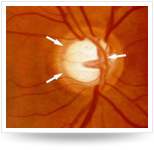

• 急性閉角型青光眼例圖